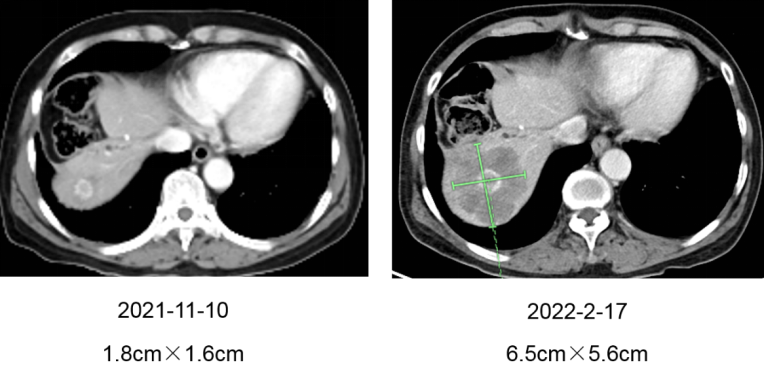

因拒绝原方案继续治疗或维持治疗,患者于2021-11-11 开始间断口服呋喹替尼(5mg,共2盒)靶向治疗共一月,因自觉无法耐受呋喹替尼遂自行口服中药2月,2022-2-17 评估:肝脏病灶明显增大至6.5cm×5.6cm,病情进展(图二)。

△图二